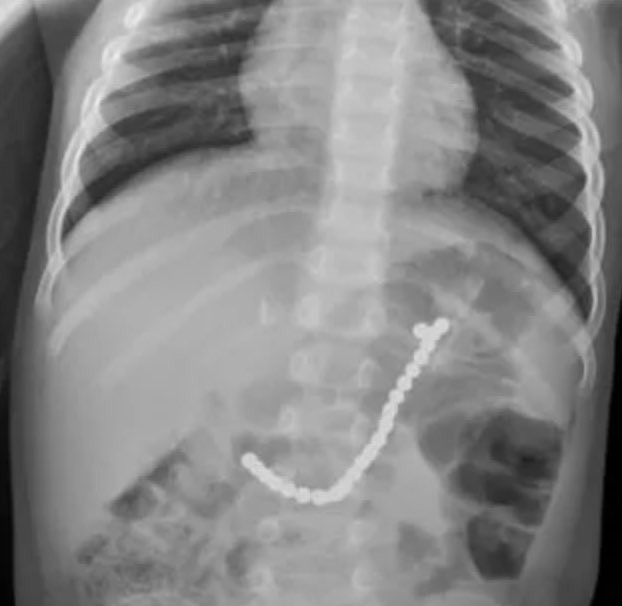

Una radiografía le salvó la vida

Caiden Cooke, de dos años de edad sufría congestión, con tos y problemas paar respirar. Preocupados, sus padres lo llevaron a urgencias. Cuando las pruebas de gripe y estreptococos salieron negativas, los médicos le hicieron una radiografía de tórax para descartar la neumonía. La prueba le salvó la vida. Según su padre, Josh Cooke:

"Fue una suerte que le hicieran esa radiografía porque descubrieron algo en su vientre. Vieron lo que parecía un brazalete de cuentas o pequeñas bolas unidas en el estómago y el intestino".

"Era urgente sacarlos. Ya se habían unido unos a otros y estaban causando dolor y dañando los tejidos".